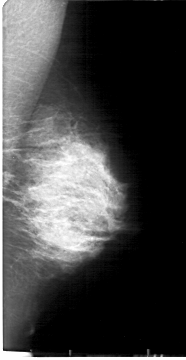

D_4169_1.RIGHT_MLO

DENSITY 4

LEFT_CC LINES 5296 PIXELS_PER_LINE 2401 BITS_PER_PIXEL 12 RESOLUTION 43.5 NON_OVERLAY

LEFT_MLO LINES 5386 PIXELS_PER_LINE 2776 BITS_PER_PIXEL 12 RESOLUTION 43.5 NON_OVERLAY

RIGHT_CC LINES 4906 PIXELS_PER_LINE 2581 BITS_PER_PIXEL 12 RESOLUTION 43.5 OVERLAY

RIGHT_MLO LINES 5266 PIXELS_PER_LINE 2851 BITS_PER_PIXEL 12 RESOLUTION 43.5 OVERLAY

FILE: D_4169_1.RIGHT_MLO.OVERLAY

TOTAL_ABNORMALITIES 1

ABNORMALITY 1

LESION_TYPE CALCIFICATION TYPE PUNCTATE DISTRIBUTION CLUSTERED

ASSESSMENT 0

SUBTLETY 3

PATHOLOGY BENIGN

FILE: D_4169_1.RIGHT_CC.OVERLAY